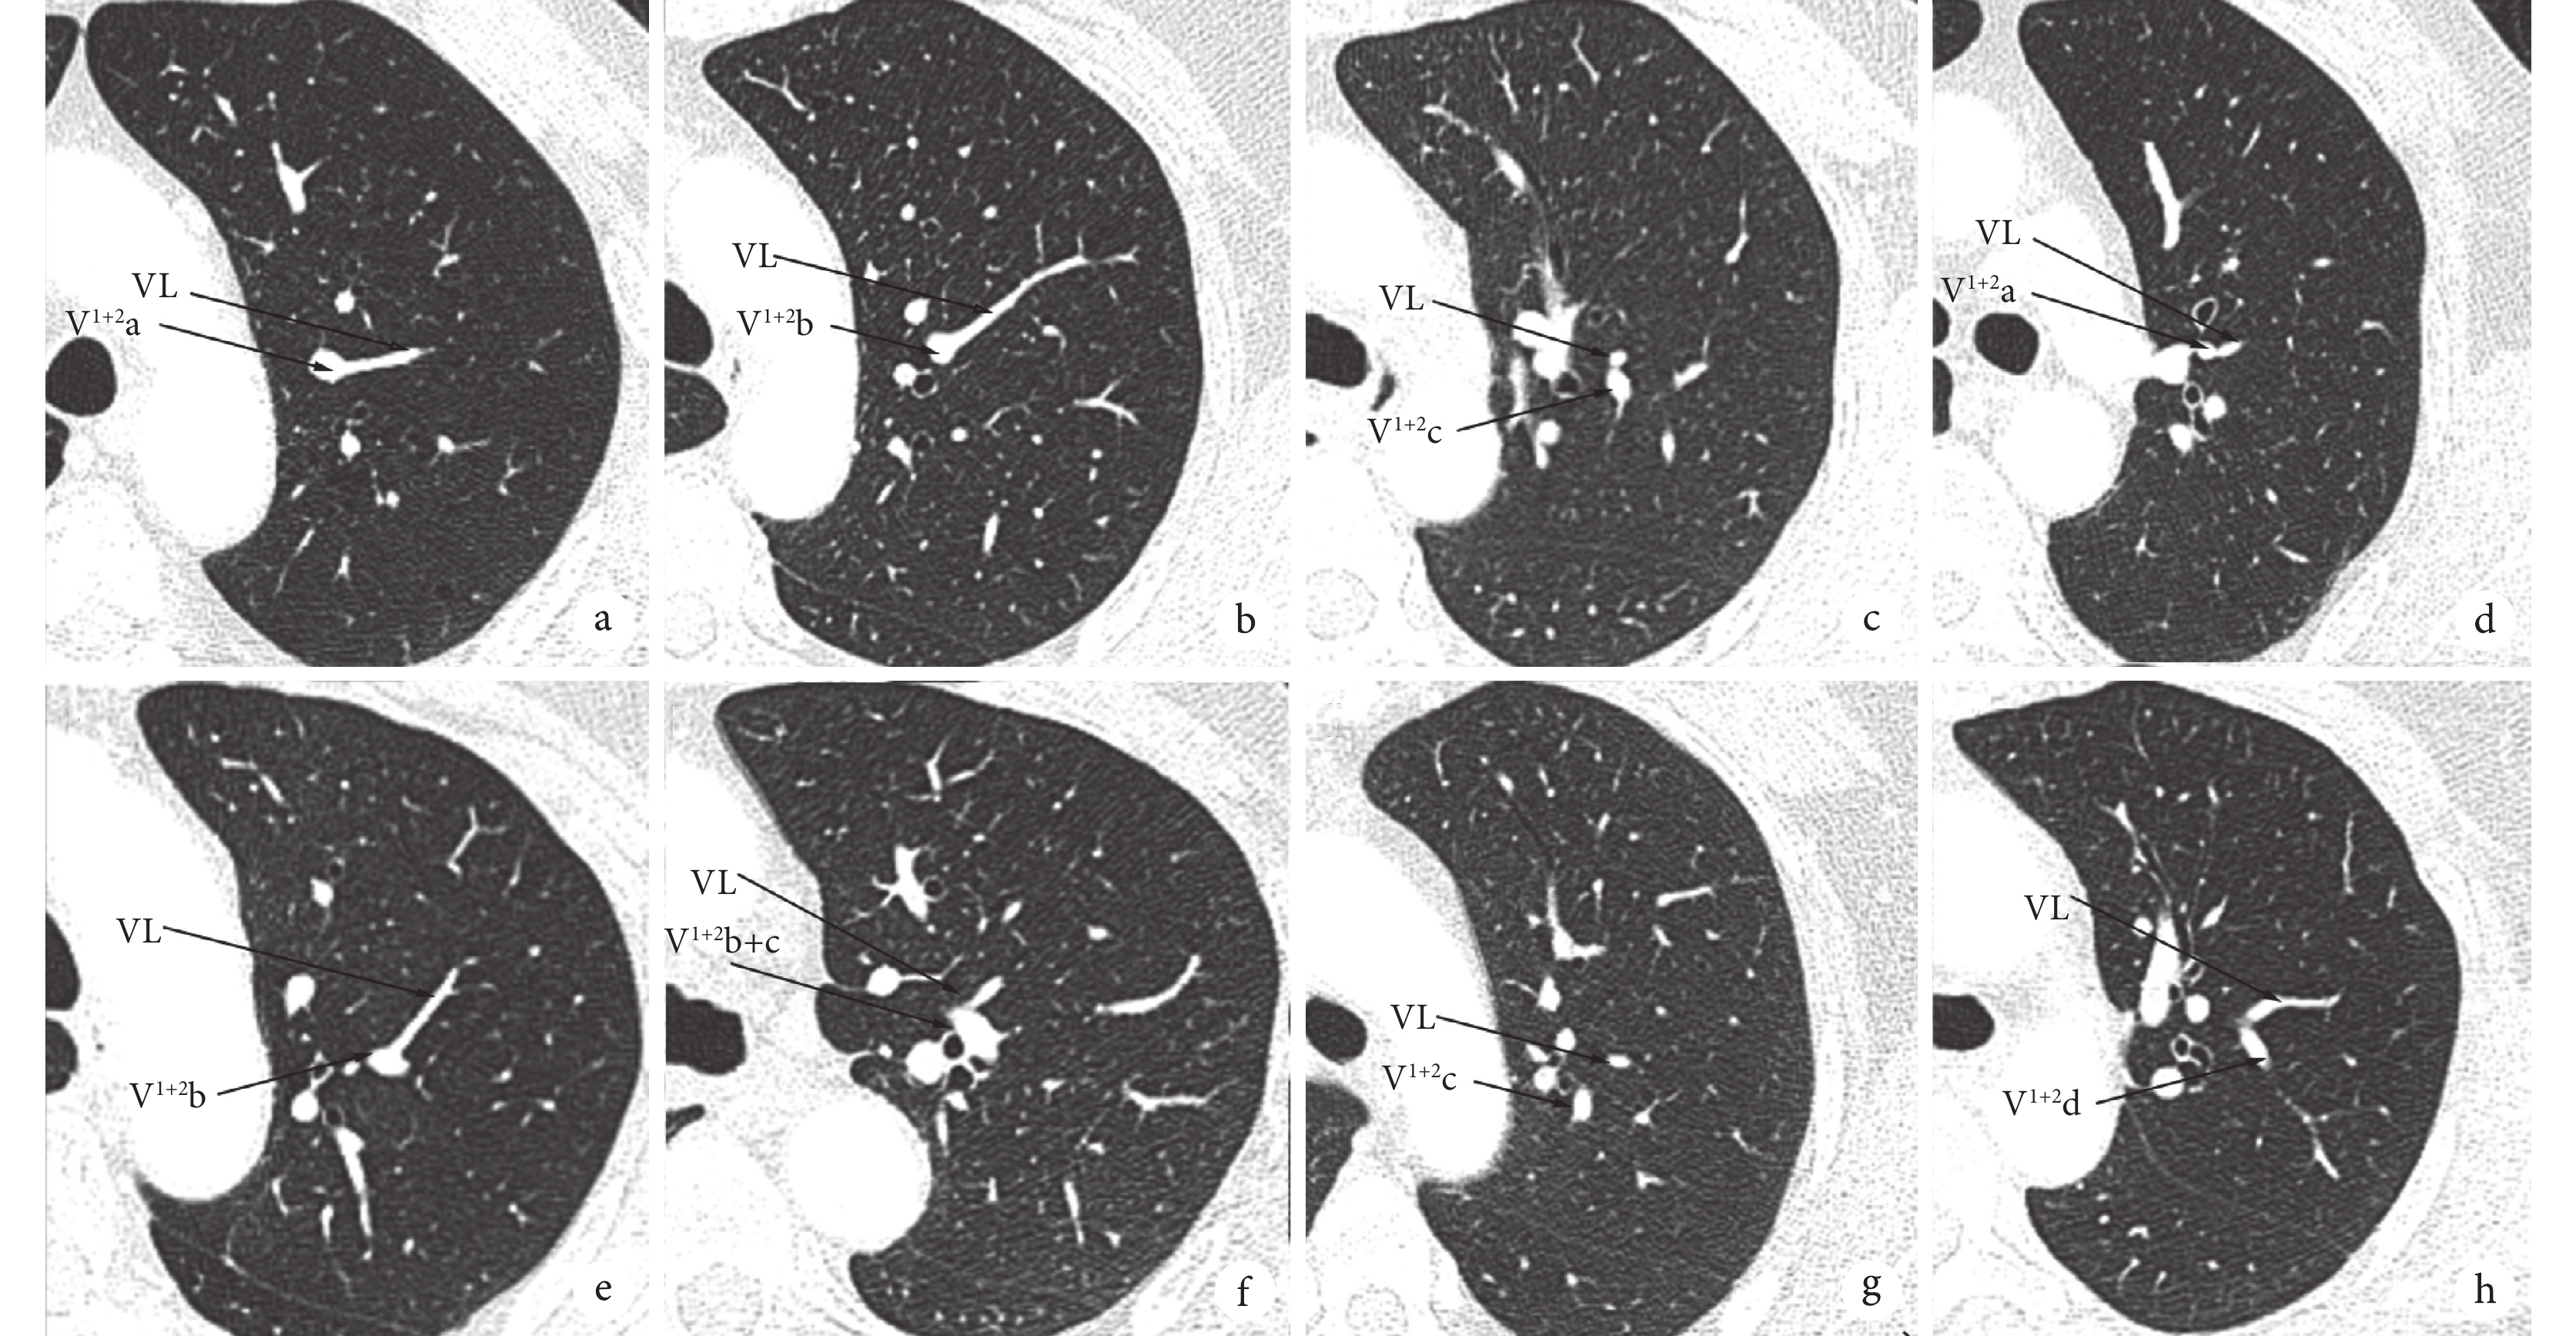

a~c:無中心靜脈型,VL依次回流至V1+2a、V1+2b、V1+2c;d~h:中心靜脈型、半中心靜脈型,VL依次回流至V1+2a、V1+2b、V1+2b+c、V1+2c、V1+2d;VL:側枝靜脈

左上肺存在VL的618例患者中,無中心靜脈型36例,其中3例VL回流至V1+2a(3/36,8.3%),14例VL回流至V1+2b(14/36,38.9%),19例VL回流至V1+2c(19/36,52.8%),未見VL回流至V1+2d。618例患者中,半中心靜脈型、中心靜脈型總計582例,其中16例VL回流至V1+2a(16/582,2.8%),88例VL回流至V1+2b(88/582,15.1%),389例VL回流至V1+2b+c(389/582,66.8%),81例VL回流至V1+2c(81/582,13.9%),8例VL回流至V1+2d(8/582,1.4%);見圖1~2。